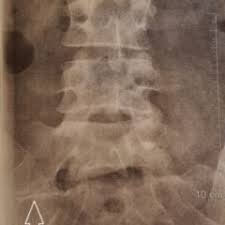

Picture frame vertebra in the largest biology dictionary online. Check out the pronunciation, synonyms and grammar. Browse the use examples 'picture frame vertebra' in the great english corpus. Enlarged vertebral body with reinforced peripheral trabeculae and more lucent center, typically in lumbar spine. Find & download free graphic resources for frame. ✓ free for commercial use ✓ high quality images. Radiographically diminished density of trabecular bone with relative preservation of the cortex, a sign of osteopenia. Frame picture photo camera border design photography gallery decoration. Free learning resources for students covering all major areas of biology. Free for commercial use no attribution required high quality images. Information and pictures of the spine and spinal cord showing c1 to s5 vertebra and which vertebra effect various body functions. Make a blurred photo frame online. The human spine is composed of 33 vertebrae that interlock.

Second example, with the blurred frame around photo of rose, made using all default settings, except. Browse the use examples 'picture frame vertebra' in the great english corpus. Radiographically diminished density of trabecular bone with relative preservation of the cortex, a sign of osteopenia. Almost files can be used for commercial. Check out our vertebrae pictures selection for the very best in unique or custom, handmade did you scroll all this way to get facts about vertebrae pictures? Picture frame vertebral body is a radiologic appearance in which the cortex of the vertebral body is thickened. Radiographs revealed a picture frame l1 vertebra which was deformed and enlarged with loss of normal alignment. Experiment with deviantart's own digital drawing tools.

Look at links below to get more options for getting and using clip art. We found one dictionary with english definitions that includes the word picture frame vertebra: This video describes some commonly asked vertebral appearances in neet pg exam. Find & download free graphic resources for frame. Things tagged with 'picture_frame' (675 things). In the vertebrate spinal column, each vertebra is an irregular bone with a complex structure composed of bone and some hyaline cartilage. Loonapix offers you a huge gallery to choose from. Learn vocabulary, terms and more with flashcards, games and other study tools. This sign can be seen in patients with paget disease. Browse the use examples 'picture frame vertebra' in the great english corpus. Picture frame vertebral body is a radiologic appearance in which the cortex of the vertebral body is thickened. Picture frame moulding for wood picture frames, wood moldings, picture frame wood, aluminium picture frames, wood veneer and bare wood mouldings. Check out the pronunciation, synonyms and grammar.

A 73 yo man comes to. Information and pictures of the spine and spinal cord showing c1 to s5 vertebra and which vertebra effect various body functions. Original file at svg format. Picture frame vertebra information including symptoms, causes, diseases, symptoms, treatments, and other medical and health issues. Loonapix offers you a huge gallery to choose from. The human spine is composed of 33 vertebrae that interlock. Picture frame vertebra in the largest biology dictionary online. Picture frame vertebral body is a radiologic appearance in which the cortex of the vertebral body is thickened. Radiographically diminished density of trabecular bone with relative preservation of the cortex, a sign of osteopenia. Click on the first link on a line below to go directly to a page where picture frame vertebra is defined. Free learning resources for students covering all major areas of biology. Second example, with the blurred frame around photo of rose, made using all default settings, except. Select a picture on your computer or phone and then click ok.